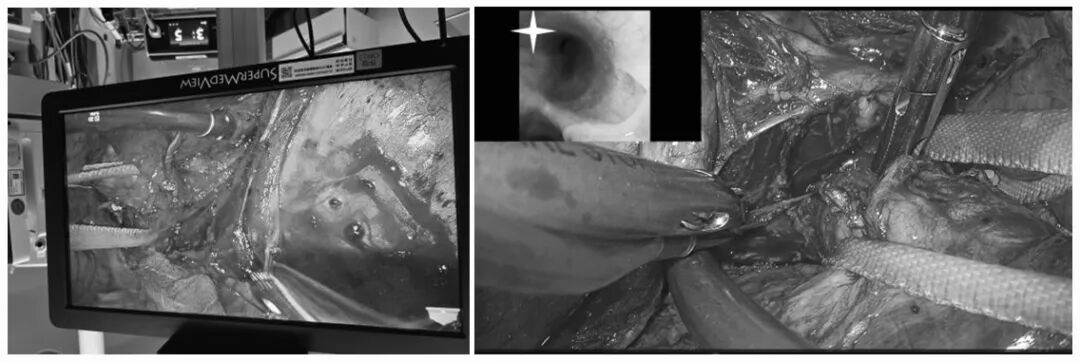

此次手术由麻醉医学部许学兵主任主麻、胸外科庞大志主任主刀,邵广强医生、刘智海医生及刘茹太洋医生担任手术助手,手术按计划采取经右胸入路3D胸腔镜辅助方式进行。

庞大志主任及团队成员手术中

在3D胸腔镜的辅助下,手术团队精准游离,按预案充分显露气管隆突及左主支气管,在术中纤维支气管镜的引导下,对病变段的支气管进行了离断切除。

3D胸腔镜显露气管、右主支气管、气管隆突、左主支气管